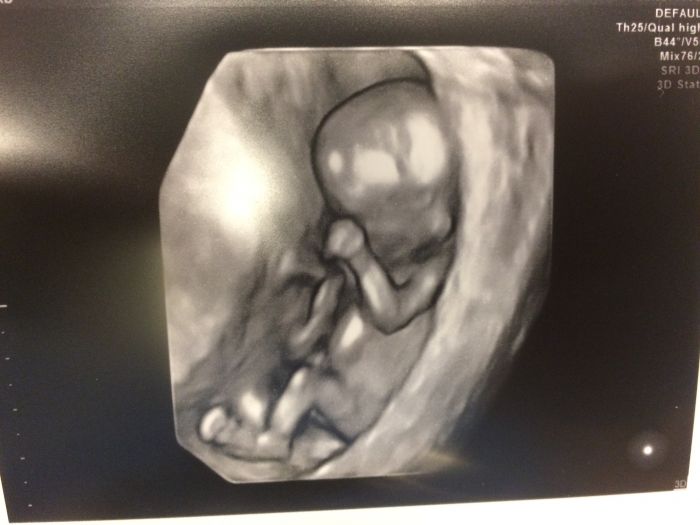

ahoooj maminky tak mam po screeningu a ulevilo se mi 93 procent ze budeme zdravoucky a cekam dalsiho pindoura prali jsme si holcicku ale co hlavne ze to bude zdravounky... uprimne se mi ulevilo ale prdolovi se nechtelo se ukazovat furt ukazoval zadicka ale pani doktorka byla mila a vse mi vysvetlovala :-) a co vy kdypak jdete drzim pesticky at mate vse v poradku :-)

Tak už mám po screeningu a teď mi volali výsledky. Takže říkali že miminko je v naprosto perfektním stavu, výsledky výborné :-D a na 90% budeme mít holčičku